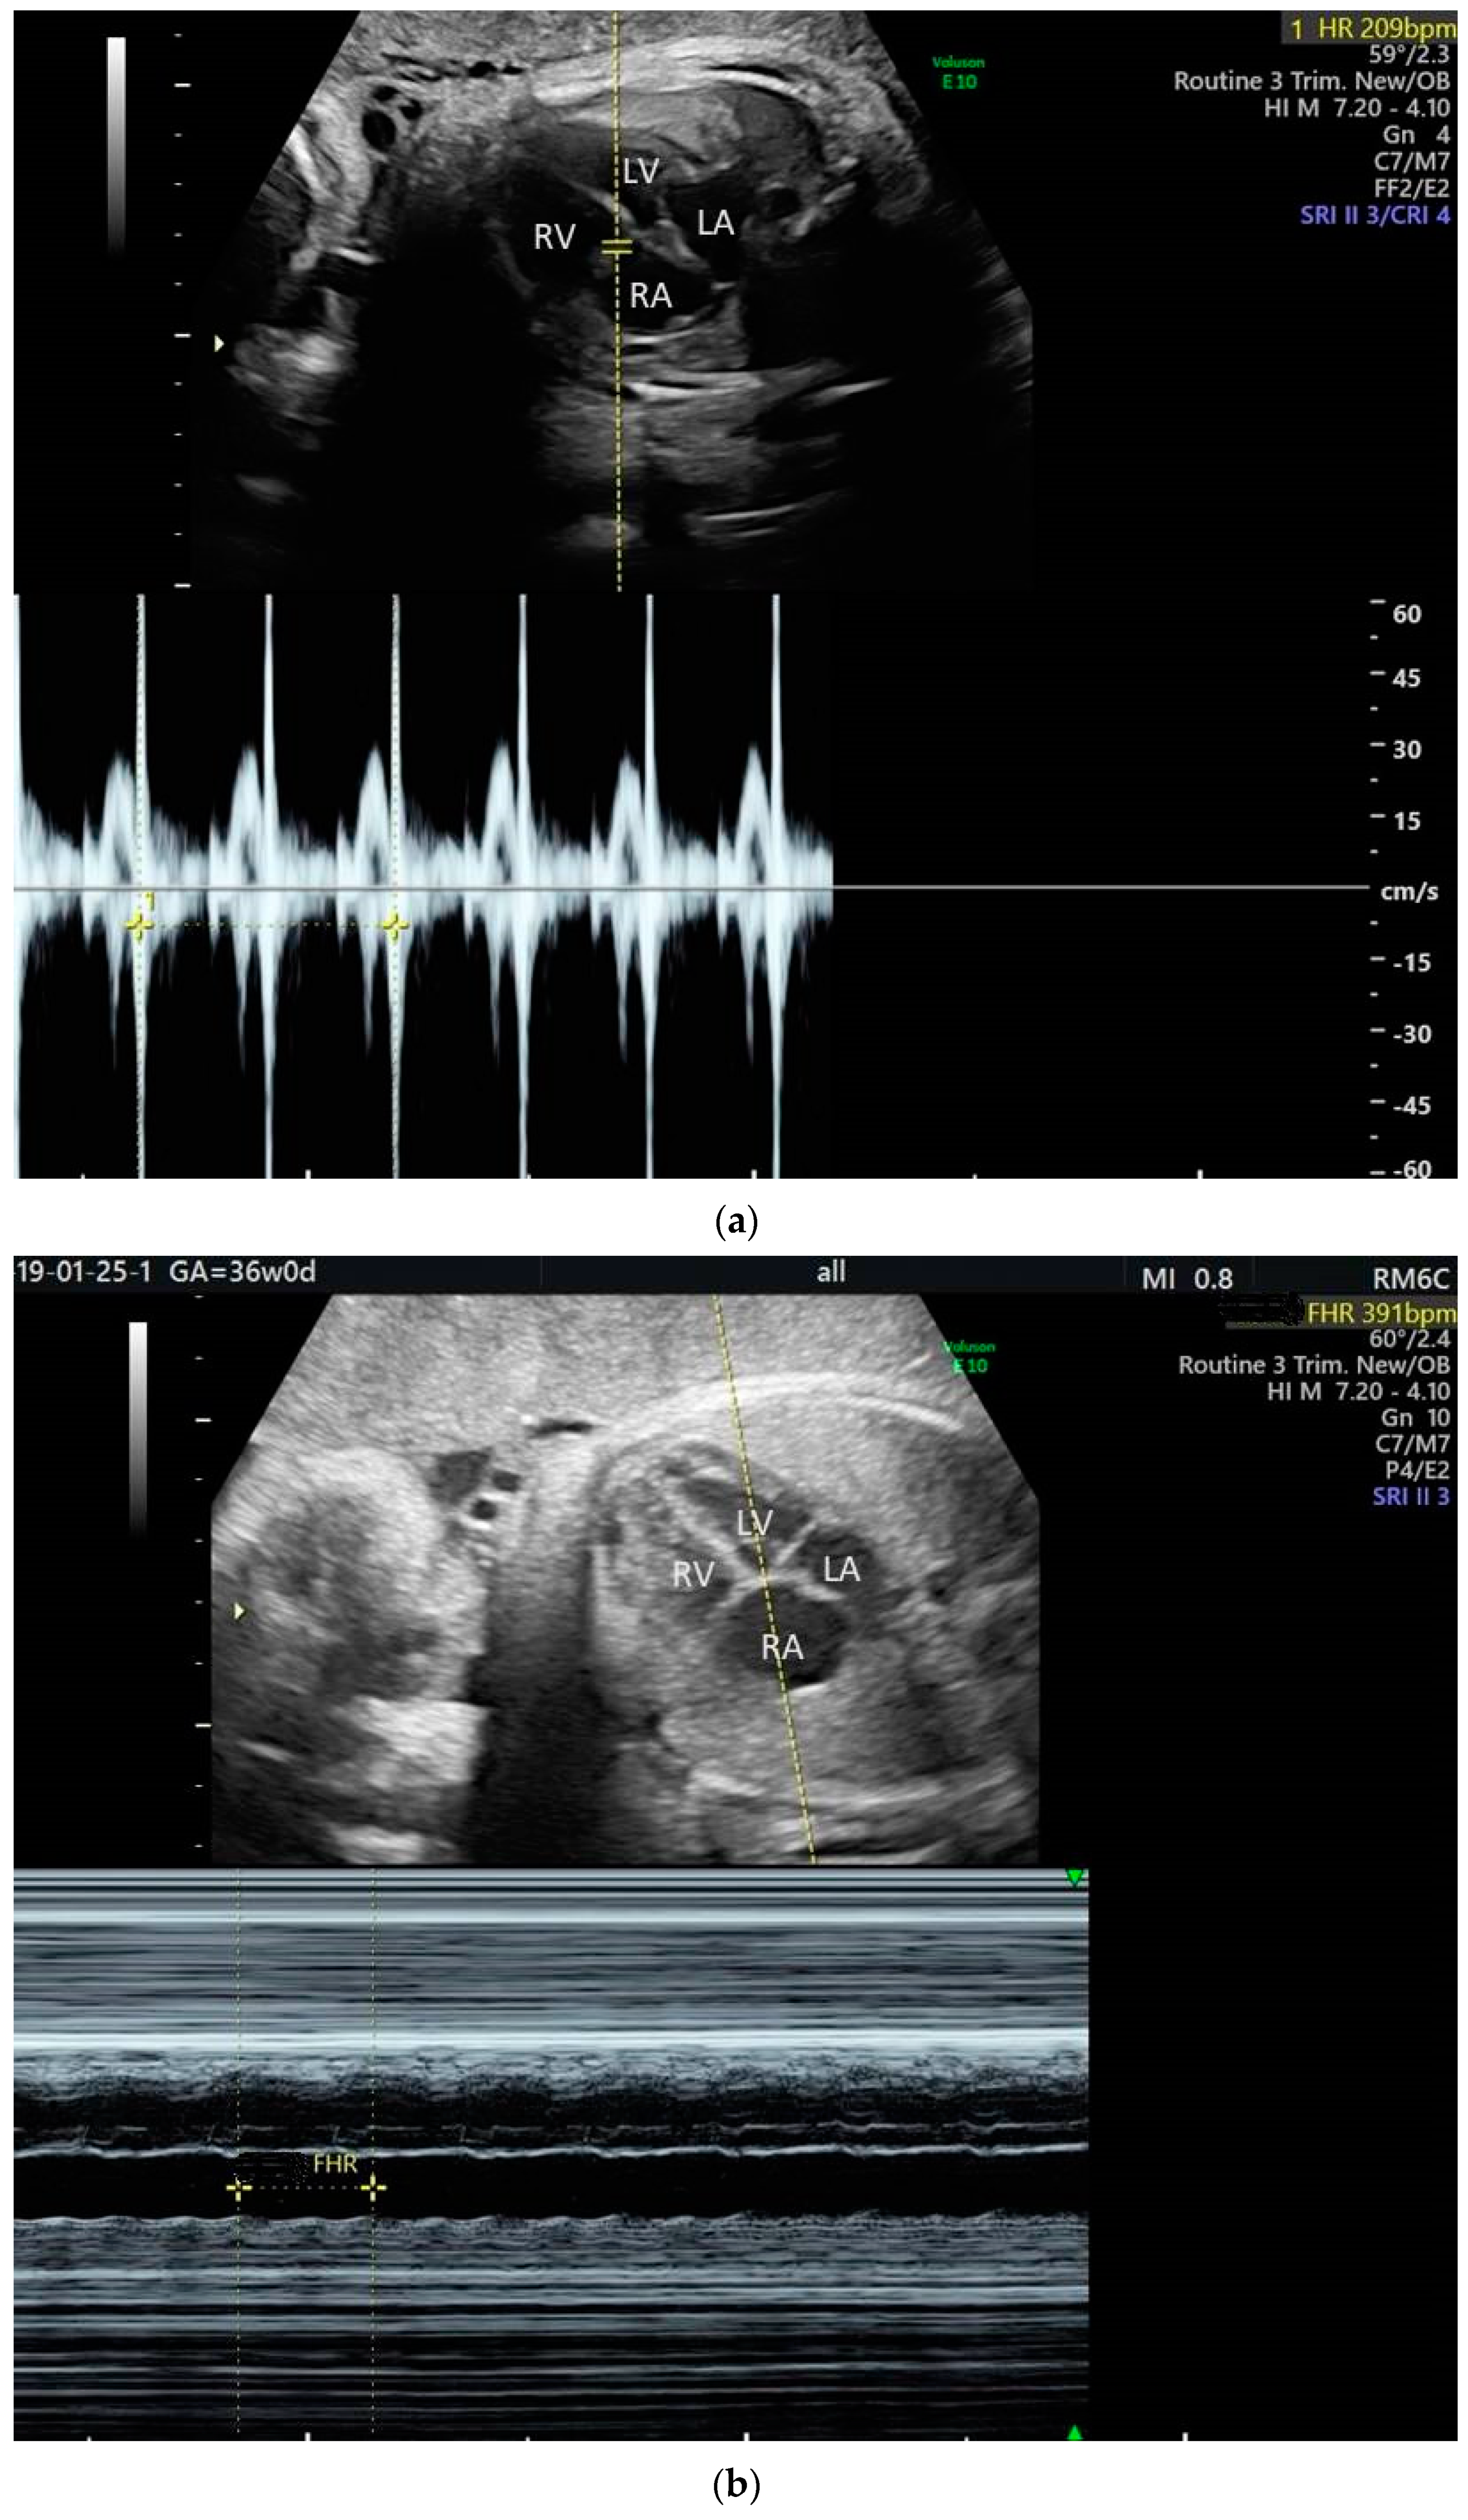

2. The Use of Ultrasound to Assess Fetal Heart Rhythm